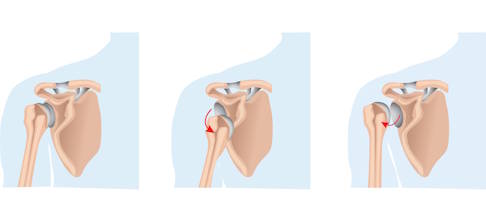

Eine Schulterluxation ist die Ausrenkung des Oberarmkopfes (Humeruskopf) aus der Gelenkpfanne (Glenoid) des Schultergelenks. Meist ist ein traumatisches Ereignis wie beispielsweise ein Sturz auf den Arm ursächlich für die Luxation der Schulter.

Eine Instabilität mit Luxationen (Ausrenkungen) der Schulter kann anlagebedingt sein, ist aber wesentlich öfter Folge einer traumatischen, unfallbedingten Erstluxation. Ein plötzlicher, unvorhergesehener Kraftimpuls führt bei einer bereits bestehenden maximalen Bewegungsauslenkung des Schultergelenks zur Schulterluxation.

Der Oberarmkopf verlässt die Gelenkpfanne und luxiert. Dabei werden im Regelfall Weichteilstrukturen abgerissen oder beschädigt. Insbesondere die bereits weite Gelenkkapsel der Schulter überdehnt und die knorpelige Lippe an der Gelenkpfanne, das Labrum glenoidale, reißt ab. Des Weiteren kann es vor allem bei älteren Patienten zu knöchernen Verletzungen mit Bruch des Oberarmkopfes oder zu einer begleitenden Ruptur der aus Sehnen bestehenden Rotatorenmanschette kommen. Diese umfasst und stabilisiert das Schultergelenk. Durch die Verletzung der Weichteilstrukturen, insbesondere des Labrums, kommt es sehr häufig zu erneuten Luxationen des Schultergelenks, auch bei Alltagstätigkeiten. Als Faustregel gilt, je jünger ein Patient bei der Erstluxation war, desto höher ist die Wahrscheinlichkeit, eine chronische, anhaltende Schulterinstabilität zu entwickeln. So zeigen Patienten, die bei der Erstluxation unter 20 Jahren waren, eine Wahrscheinlichkeit von über 80 % für eine erneute Luxation.